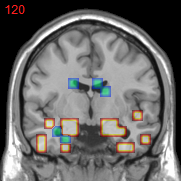

Figure 3: Stability of selected voxels across different folds of the cross-validation. The results of 5 different folds are shown in (a)-(e). The voxels with positive β𝛽\beta are in brown, negative ones are in blue. The common/overlapped voxels selected in all 10 folds are shown in green (f). The top row illustrates voxels selected by the lasso model, the mid row illustrates those of GFL and the bottom row shows those of n2superscript𝑛2n^{2}GFL.

Feature Stability. In Figure 3, we show the selected voxels across different folds of CV333Here, parameters were determined by accuracy. Similar results were observed using parameters producing same level of sparsity.. As shown, the selected voxels by lasso vary much across different folds, whereas the selected voxels by GFL are more stable. However, by assuming the positive correlation between the features and the disease labels in n2superscript𝑛2n^{2}GFL, we further increase the stability. To quantitatively evaluate the stability gain, we denote the variables of the k𝑘kth fold of CV as 𝜷(k)𝜷𝑘\boldsymbol{\beta}(k). We introduce two measurements here. In (?), the Estimation Stability (ES) is proposed to measure the stability of the estimation

where ##\# is the number of elements in a set. In Tab. 3, both measurements quantitatively suggest n2superscript𝑛2n^{2}GFL obtains much more stable voxels due to the consideration of the correlation between the features and the disease labels 444We notice that, in (?), the stability is computed using the top 50 positive voxels because these voxels are believe to be the most atrophied ones. By computing the stability of all non-zero voxels, the mDC of GFL drops around 30%percent3030\%. This clearly shows that the instability is caused largely by the undesirable voxels that disagree with the correlation prior (those scattered blue voxels in the mid row)..